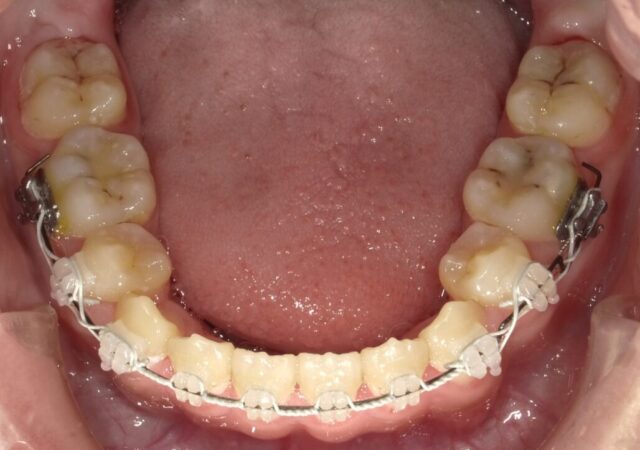

≪下顎咬合面観≫

2023年5月

2025年1月